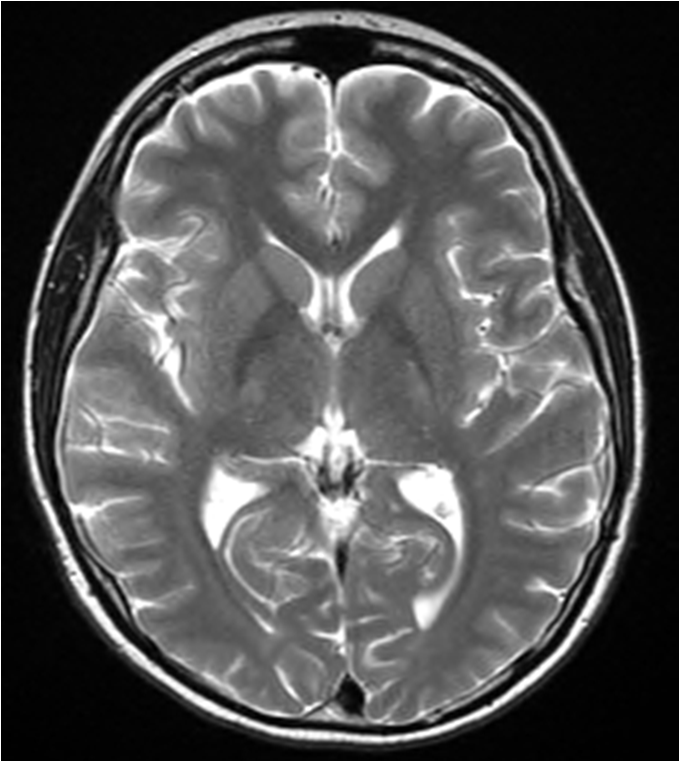

Popis jednotlivých částí

1. Corpus callosum

2. Nucleus caudatus

3. Septum pellucidum

4. Fornix

5. Globus pallidus

6. Putamen

7. Capsula interna

8. Thalamus

9. Commissura habenularum

10. Hippocampus